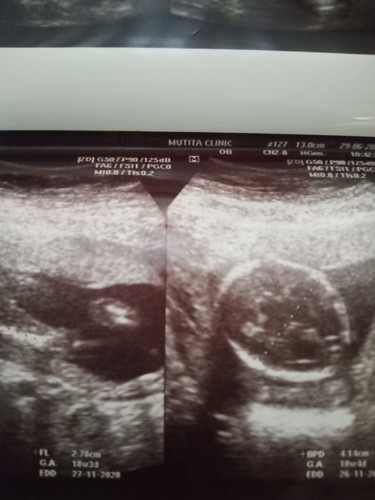

เพื่อนๆช่วยดูหน่อยค่ะว่าเป็นผู้หญิงหรือเป็นผู้ชาย

คุณหมอบอกว่า ไม่เห็นจู๋นะคะน่าจะเป็นผู้หญิงค่ะ ช่วยดูหน่อยค่ะ ว่าเป็นผู้หญิงหรือเป็นผู้ชาย

ดูไม่ออกเลยค่ะแม่ รูปไม่ค่อยชัด อีกอันเป็นรูปหัว